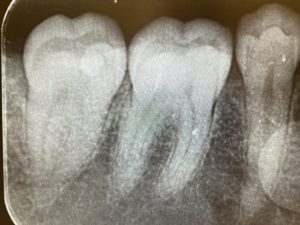

歯医者さんのレントゲン④(CT撮影)📸

本日は3つ目のレントゲン、

『CT撮影』についてのお話です📸

CT撮影とはパノラマ写真と同じような装置ですが、立体的に撮影をするので、前後、左右、上下から見た情報が得られます😲✨

CT写真とはこのようなものです!

一見しただけではどのようになっているか難しいですね…😅💦

ですが先生が分かりやすくお話してくれますので治療の際はご安心してくださいね😊

さて、CT写真はどのようなときに撮影するものなのかというと、、、🤔🤔

親知らずを抜く際に、顎の下の神経【下顎神経】に近そうな場合や、【副鼻腔】というお鼻の空洞に近そうな場合に撮ることが多いです😊

撮らなくても安心して抜ける場合もあるので、その場合は撮らないこともあります💁

先程のCT写真は、親知らずの抜歯をする前に撮った写真です!

上から見た図や横から見た図、3Dで写されているものを見ると、斜めに生えていることや、他の歯と比べて骨に埋まっていることが分かりますね

また、根幹治療という根っこの治療の際、治療の際に使用している拡大鏡でも見えないくらい根っこの管が細くなってしまっていたり、根の形が複雑だったりする場合もCT写真で根の状態を確認することがあります!

CT写真は3次元的に撮る撮影法なので、パノラマ写真やデンタル写真よりもさらに細かく確認することができるんですね😲✨